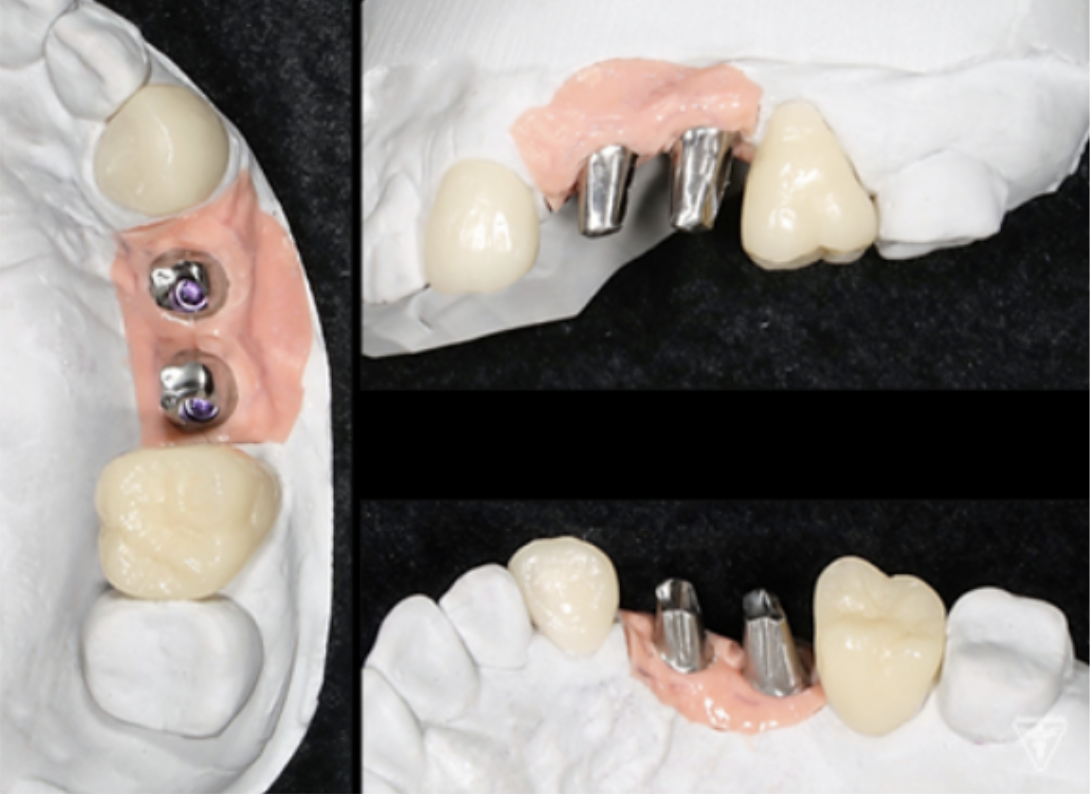

インプラント

サージカルガイドの作成

インプラント埋入前のCTによる確認

最終補綴物装着時